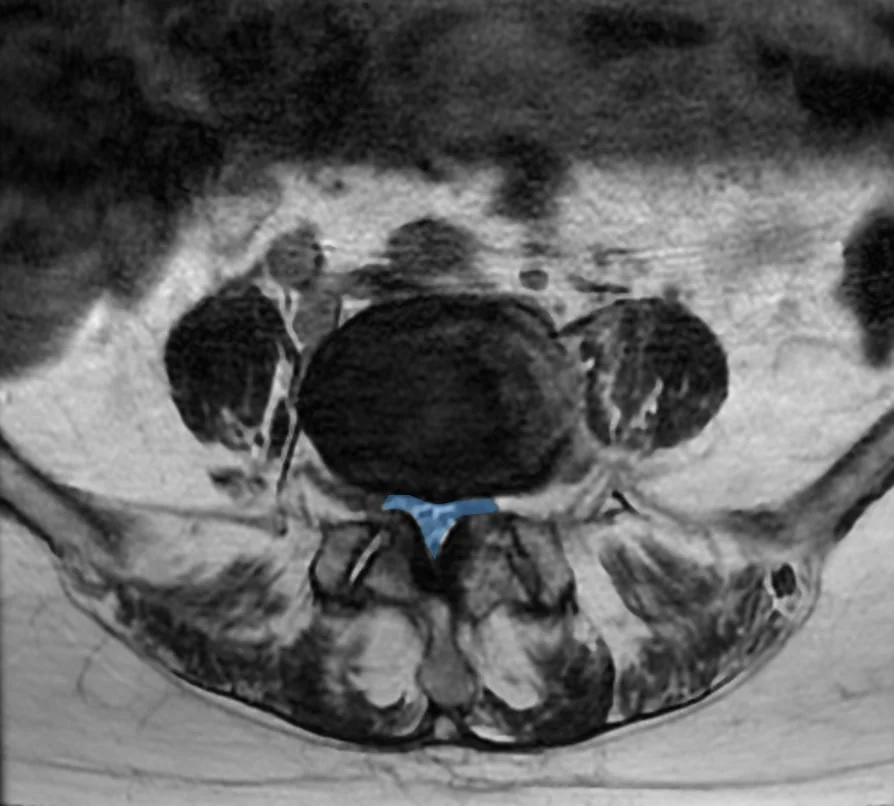

À droite : canal lombaire étroit (en bleu) où les racines nerveuses sont comprimées.